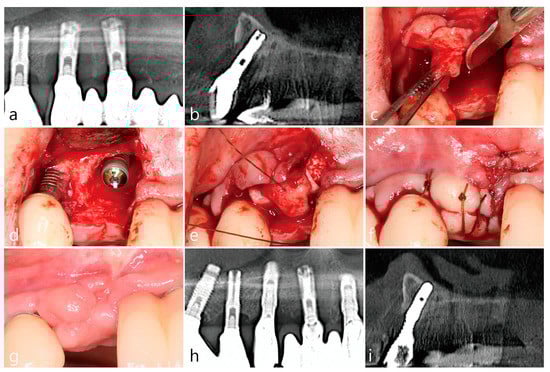

3. Case 1

- A tooth or implant with severe bone loss was removed using extraction forceps under local anesthesia with 2% lidocaine containing 1:100,000 epinephrine;

- A midcrestal incision and two buccal vertical incisions were made. Before raising the flap, special care was taken to ensure a clean dissection of the IGT from the underlying flap without any damage and the IGT is still well-attached to the flap. The IGT was then further separated from the bony housing by using a curette with various curvatures and a periosteal elevator.

- The IGT attached to the buccal flap was dissected to an appropriate thickness using a #15 blade so that the base of the IGT was still attached to the existing flap, and the flap was eventually extended. Periosteal releasing incisions were not performed at the flap base.

- The extraction socket was thoroughly debrided using a Molt curette and a titanium brush.

- A surgical guided stent was used so that the implant (Implantium, Dentium, Suwon, Korea) was placed 2.0 mm subcrestal to the level of the adjacent bone in the extraction socket.

- A synthetic osteoconductive bone graft substitute composed of hydroxyapatite (HA) and beta-Tricalcium phosphate (β-TCP) (Osteon III, Genoss, Suwon, Korea) and a resorbable collagen membrane (Genoss, Suwon, Korea) were placed to cover the implant and the peri-implant osseous defect.

- After covering the bone graft with the collagen membrane, the extended IGT was sutured with the palatal flap with 4-0 Catgut. Next, the buccal flap was closed using 4-0 nylon or black silk.

- Uncovering procedures were performed 4–6 months after initial surgery. Under local anesthesia, the buccal flap was reflected, the regenerated tissue above the implant cover screw was removed, and the healing abutment was connected to the implant. The buccal flap was closed using 4-0 Catgut or black silk. Antibiotics and anti-inflammatory drugs were prescribed for 5 days. The prosthesis was installed 2 months after uncovering.